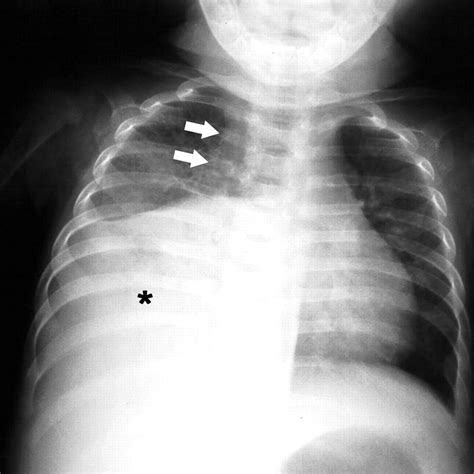

Interpreting Tb X Ray results requires expertise and experience. Radiologists look for specific signs that may indicate TB:

• Cavities: These are hollow spaces in the lungs that can form as the body tries to contain the infection.

• Nodules: Small, round opacities that can be indicative of TB infection.

• Infiltrates: Areas of increased density in the lung tissue, often seen in active TB.

• Pleural Effusion: Fluid accumulation in the pleural space, which can be a complication of TB.